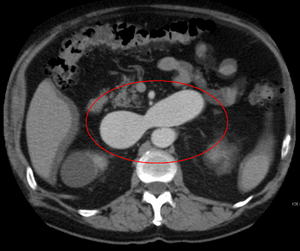

يتم تشخيص التشوه الشرياني الوريدي بشكل أساسي من خلال طرق التصوير التالية:

- التصوير المقطعي المحوسب (CT) هو عبارة عن أشعة سينية غير باضعة لعرض الهياكل التشريحية داخل الدماغ لاكتشاف الدم في الدماغ أو حوله. تتضمن تقنية أحدث تسمى تصوير الأوعية المقطعية المحوسبة حقن التباين في مجرى الدم لعرض شرايين الدماغ. يوفر هذا النوع من الاختبارات أفضل صور الأوعية الدموية من خلال تصوير الأوعية والأنسجة الرخوة من خلال التصوير المقطعي المحوسب.

- يعد التصوير بالرنين المغناطيسي (MRI) اختبارًا غير باضع ، يستخدم مجالًا مغناطيسيًا وموجات تردد الراديو لإعطاء رؤية مفصلة للأنسجة الرخوة للدماغ.

- تصوير الأوعية بالرنين المغناطيسي (MRA) - فحوصات تم إنشاؤها باستخدام التصوير بالرنين المغناطيسي لتصوير الأوعية الدموية وهياكل الدماغ على وجه التحديد. يمكن أن يكون تصوير الأوعية بالرنين المغناطيسي إجراءً جائرًا ، يتضمن إدخال صبغات التباين (على سبيل المثال ، عوامل تباين الجادولينيوم MR) في الأوعية الدموية للمريض باستخدام قسطرة يتم إدخالها في الشريان وتمريرها عبر الأوعية الدموية إلى الدماغ. بمجرد وضع القسطرة في مكانها ، يتم حقن صبغة التباين في مجرى الدم ويتم التقاط صور التصوير بالرنين المغناطيسي. بالإضافة إلى ذلك أو بدلاً من ذلك ، يمكن استخدام تقنيات التصوير بالرنين المغناطيسي المعتمدة على التدفق أو غيرها من تقنيات التصوير بالرنين المغناطيسي لتحديد الموقع والخصائص الأخرى للأوعية الدموية